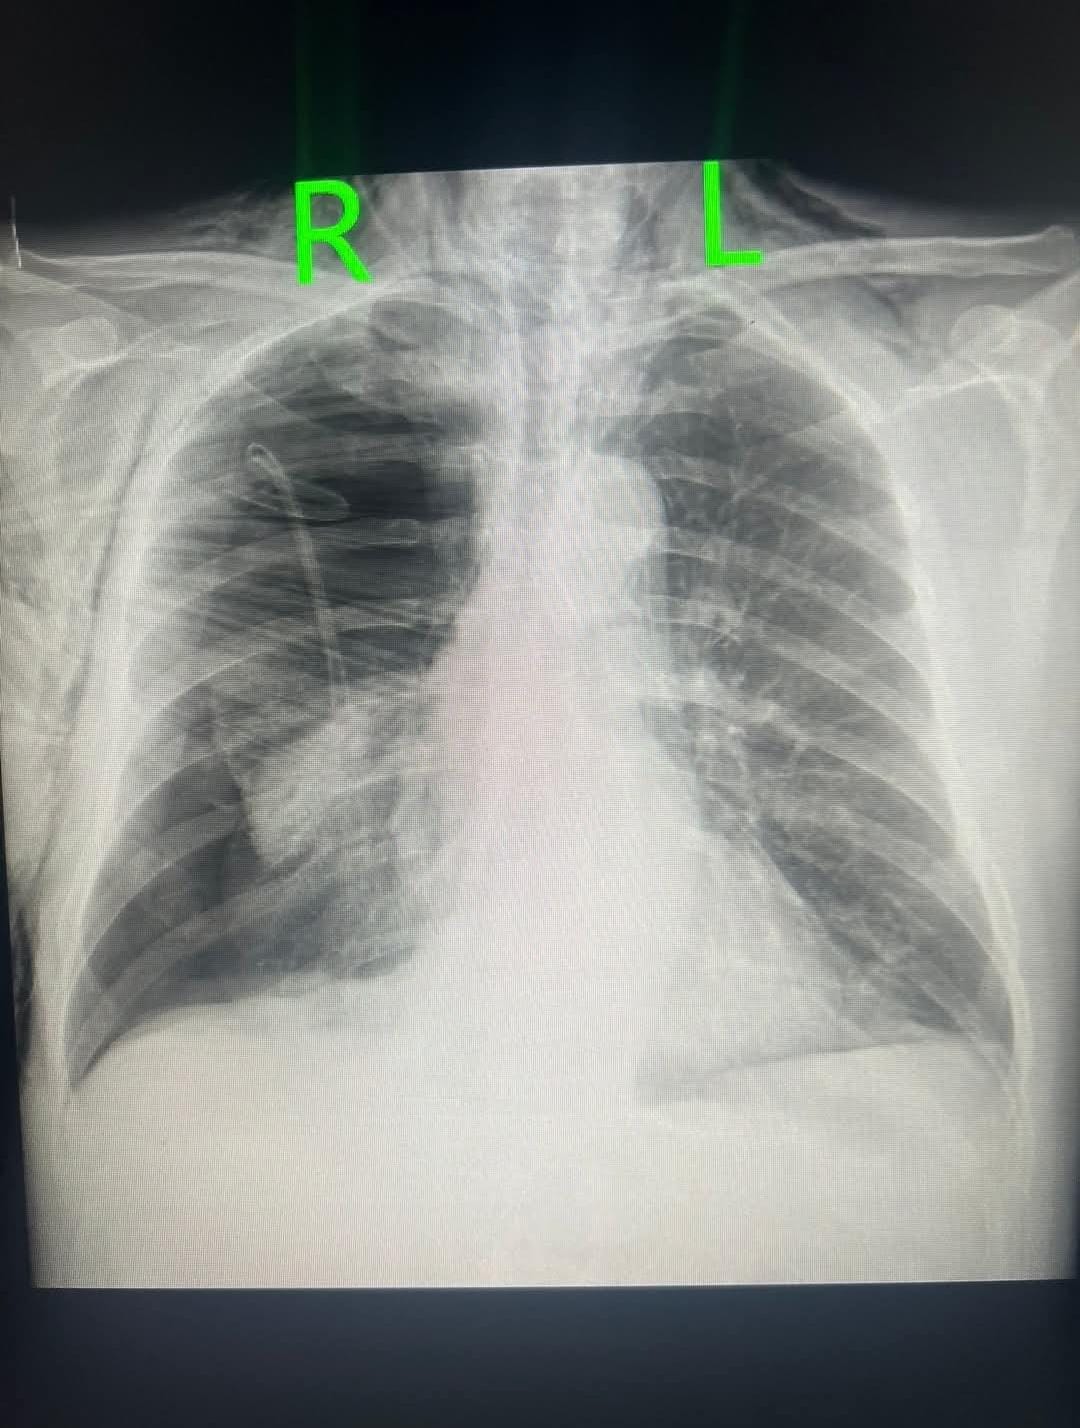

Tribuna.az xəbər verir ki, görüntüləri həkim Aydın Əliyev paylaşıb. O bildirib ki, günə 2 qutudan artıq siqaret çəkən pasiyentin sağ ağciyəri içəridən deşilib:

“Nəfəs aldığı hava plevra boşluğuna daxil olub ağciyəri sıxıb büzüşdürüb-total kollaps (spontan tension pnevmotoraks) olub. Sağ plevra boşluğundakı havanın çıxması üçün bülau drenajı qoyulub, fəqət drenajın plevra boşluğundakı hissəsi qatlanıb oradakı havanın çıxmasına mane olub. Deşilmiş ağciyərdən plevra boşluğuna daxil olan havanın təzyiqi artaraq bu dəfə drenaj dəliyindən döş qəfəsi divarındakı dəlikdən yumşaq toxumalar arasına daxil olaraq dərialtı emfizema-subcutaneous emphysema yaradıb”.

Həkimin paylaşdığı görüntüləri təqdim edirik: